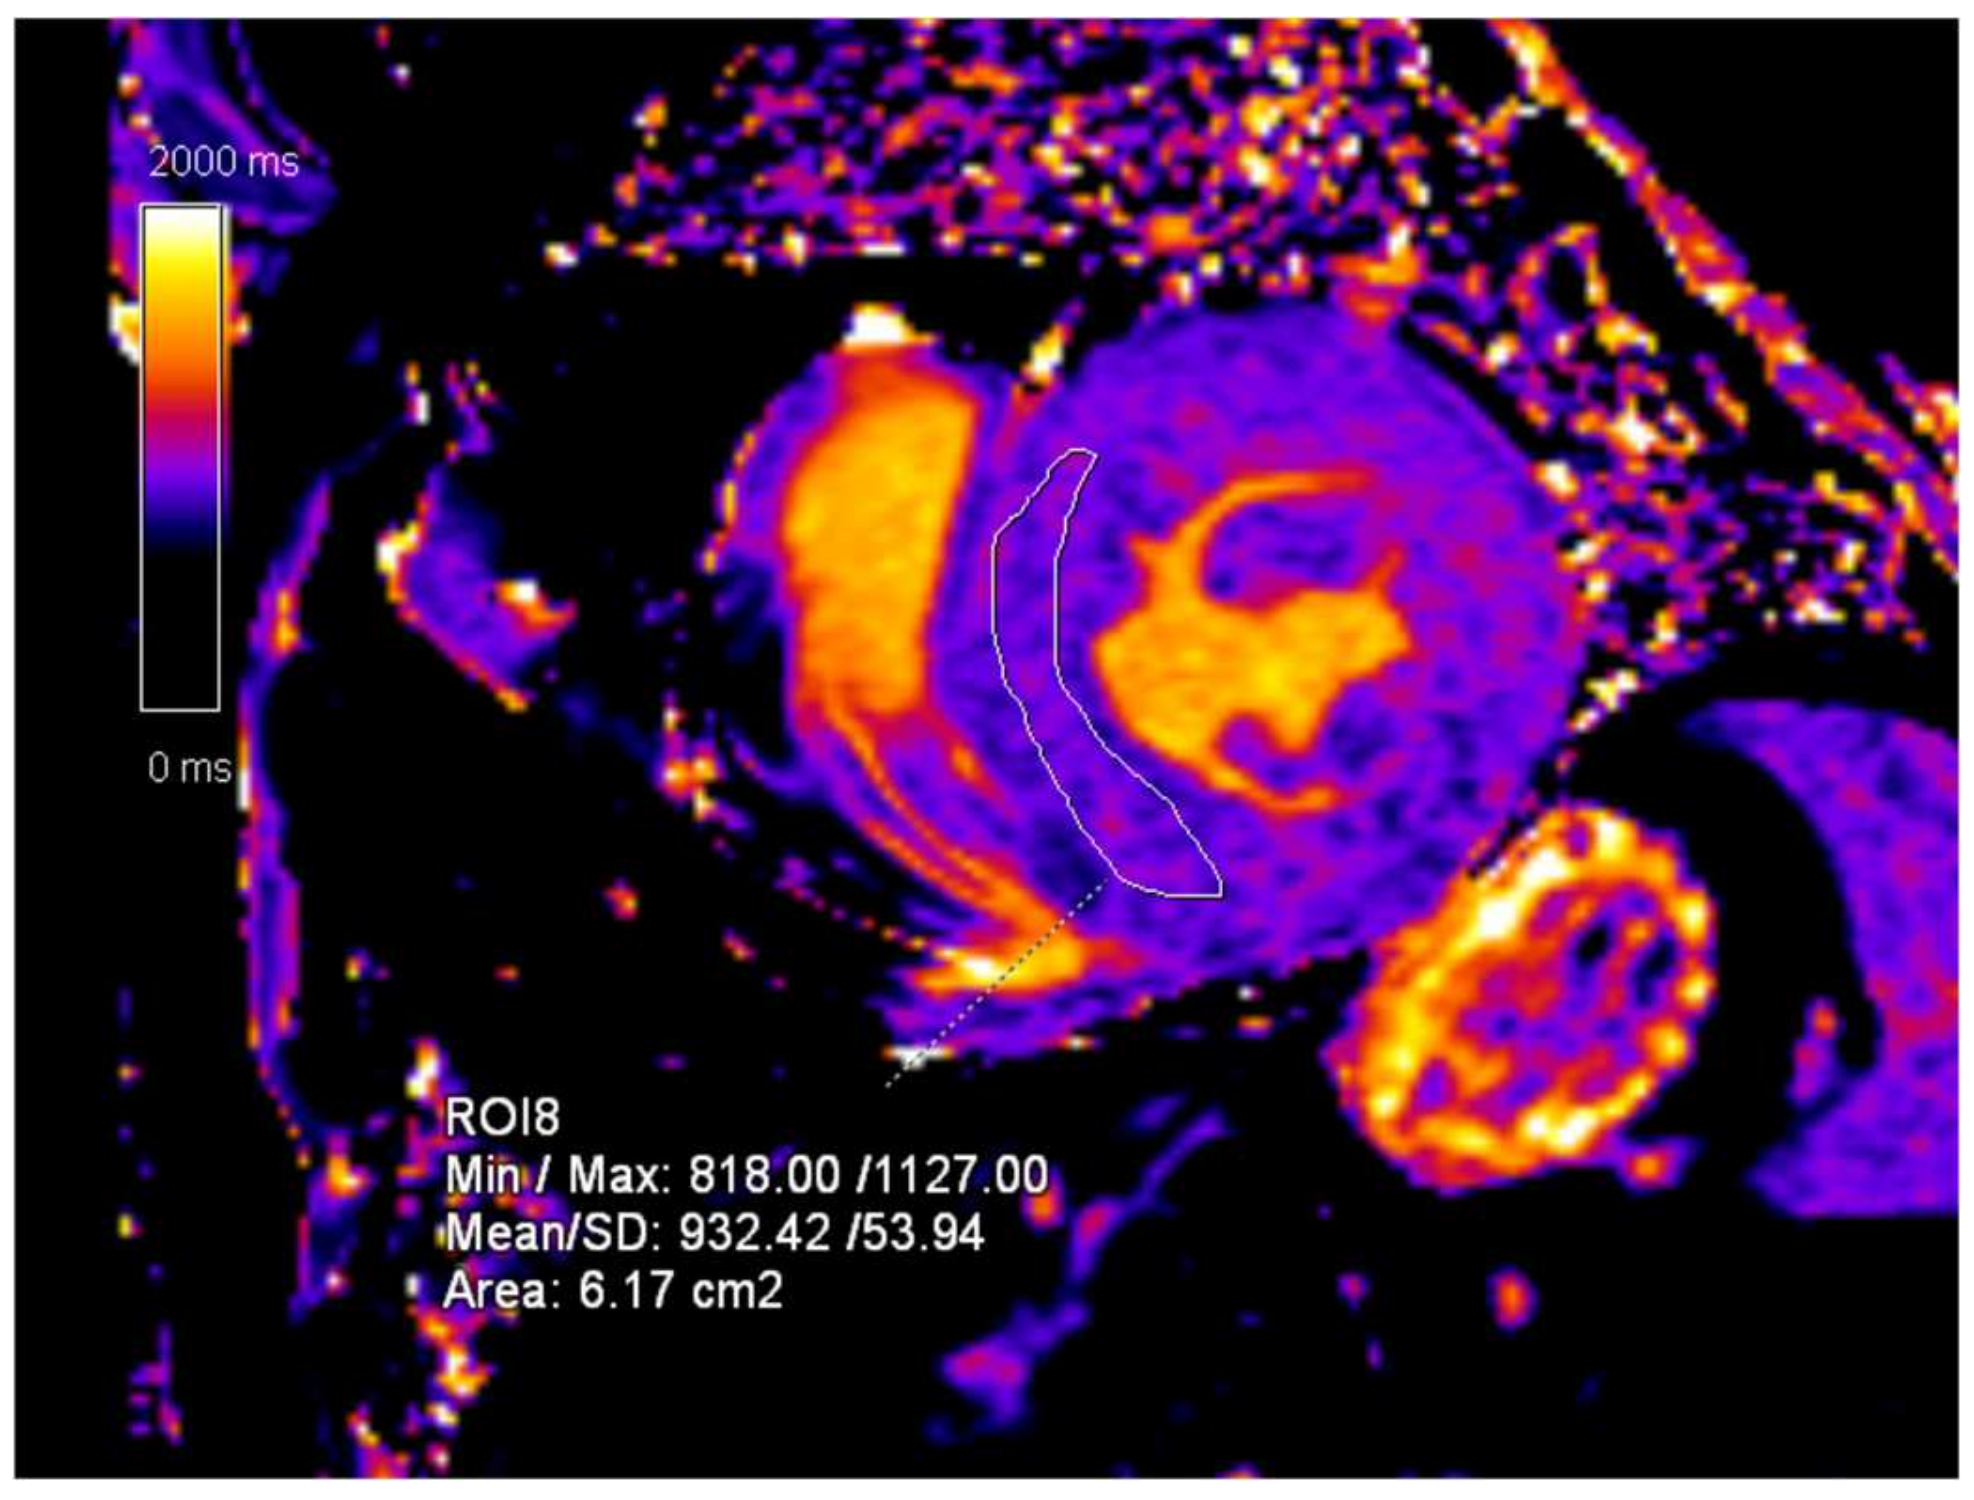

2. Case Presentation